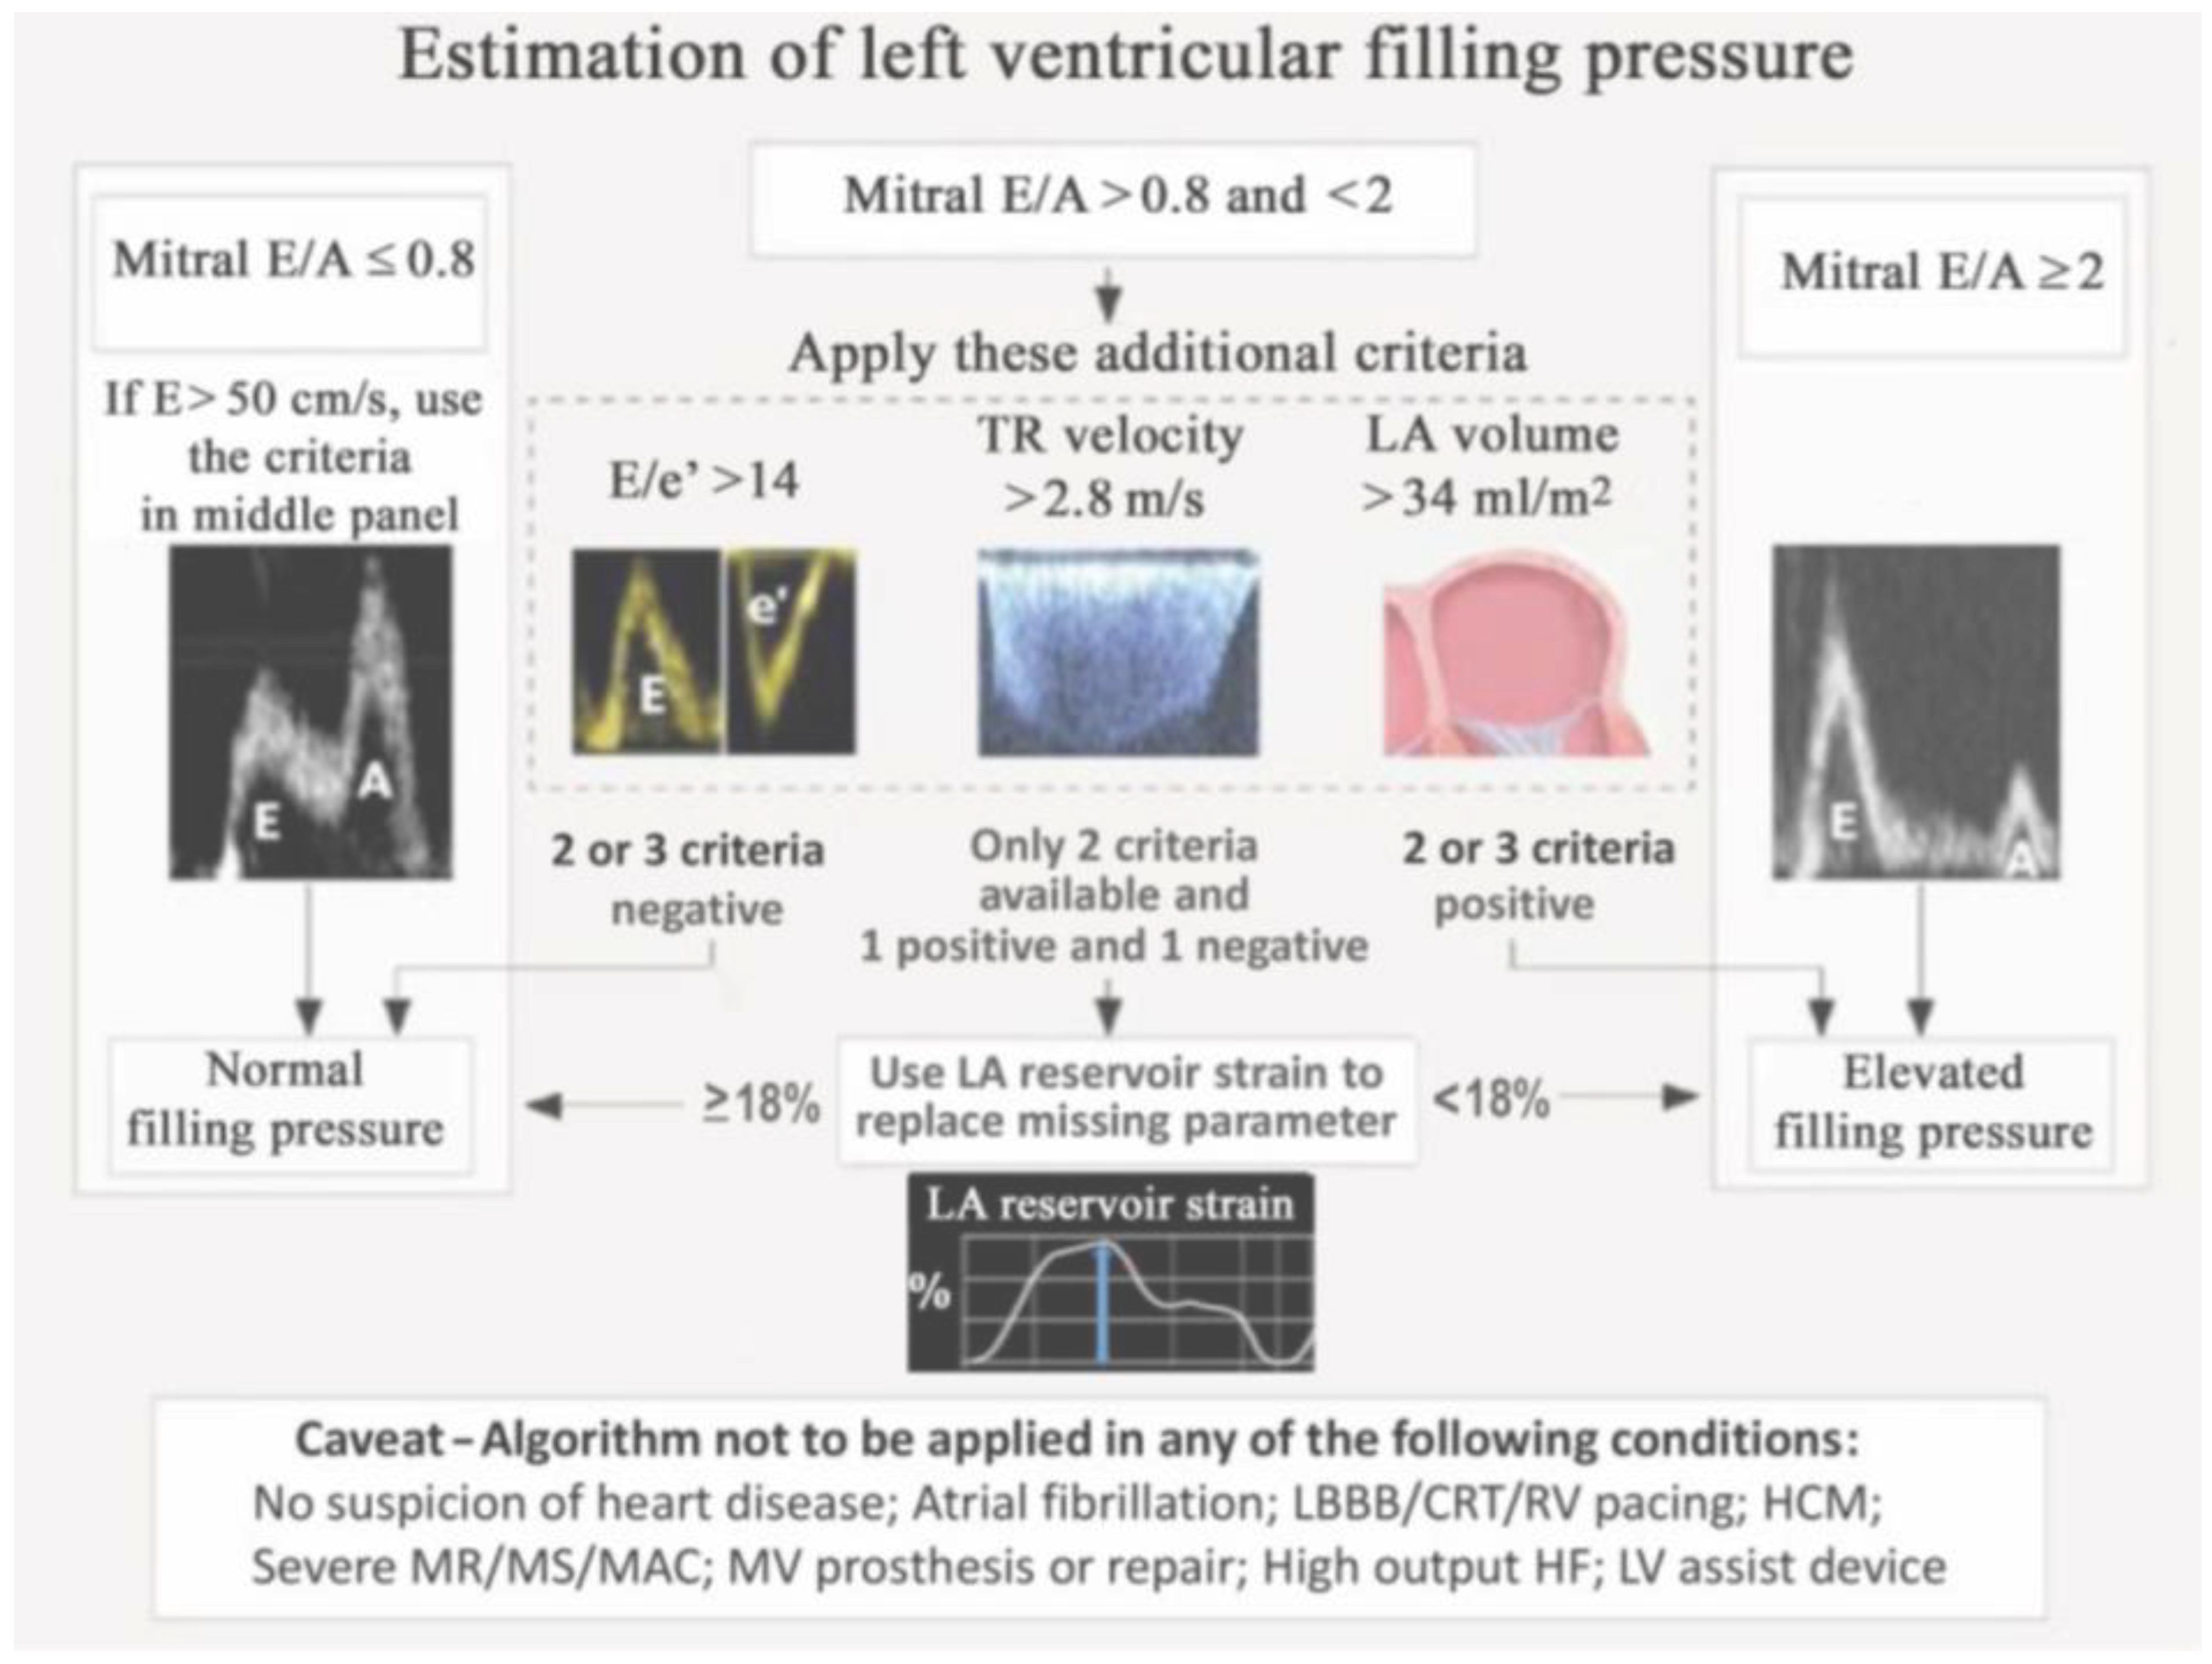

- Andersen, O.S.; Smiseth, O.A.; Dokainish, H.; Abudiab, M.M.; Schutt, R.C.; Kumar, A.; Sato, K.; Harb, S.; Gude, E.; Remme, E.W.; et al. Estimating left ventricular filling pressure by echocardiography. J. Am. Coll. Cardiol. 2017, 69, 1937–1948. [Google Scholar] [CrossRef]

- Pak, M.; Kitai, T.; Kobori, A.; Sasaki, Y.; Okada, T.; Murai, R.; Toyota, T.; Kim, K.; Ehara, N.; Kinoshita, M.; et al. Diagnostic Accuracy of the 2016 Guideline-Based Echocardiographic Algorithm to Estimate Invasively-Measured Left Atrial Pressure by Direct Atrial Cannulation. J. Am. Coll. Cardiol. Img. 2022, 15, 1683–1691. [Google Scholar] [CrossRef] [PubMed]

- Inoue, K.; Khan, F.H.; Remme, E.W.; Ohte, N.; Garcıa-Izquierdo, E.; Chetrit, M.; Moñivas-Palomero, V.; Mingo-Santos, S.; Andersen, Ø.S.; Gude, E.; et al. Determinants of left atrial reservoir and pump strain and use of atrial strain for evaluation of left ventricular filling pressure. Eur. Heart J. Cardiovasc. Imaging 2021, 23, 61–70. [Google Scholar] [CrossRef] [PubMed]